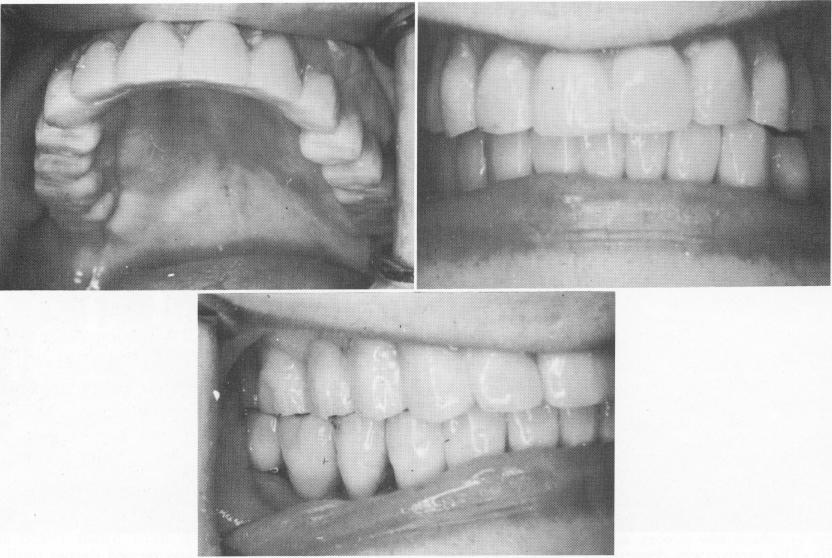

After the site had healed (Fig. 11-174), impressions were taken for the fabrication and completion of an acrylic-over-gold full arch splint. This was permanently seated with hard cement (Fig. 11-175) .

Fig. 11-174. The healed site.

Fig. 11-175. The completed acrylic prosthesis cemented in place.

1 Tissues closed after blades inserted in maxillary arch

2 Healed site in maxilla after insertion of blade implants

3 Completed maxillary acrylic prosthesis cemented in place